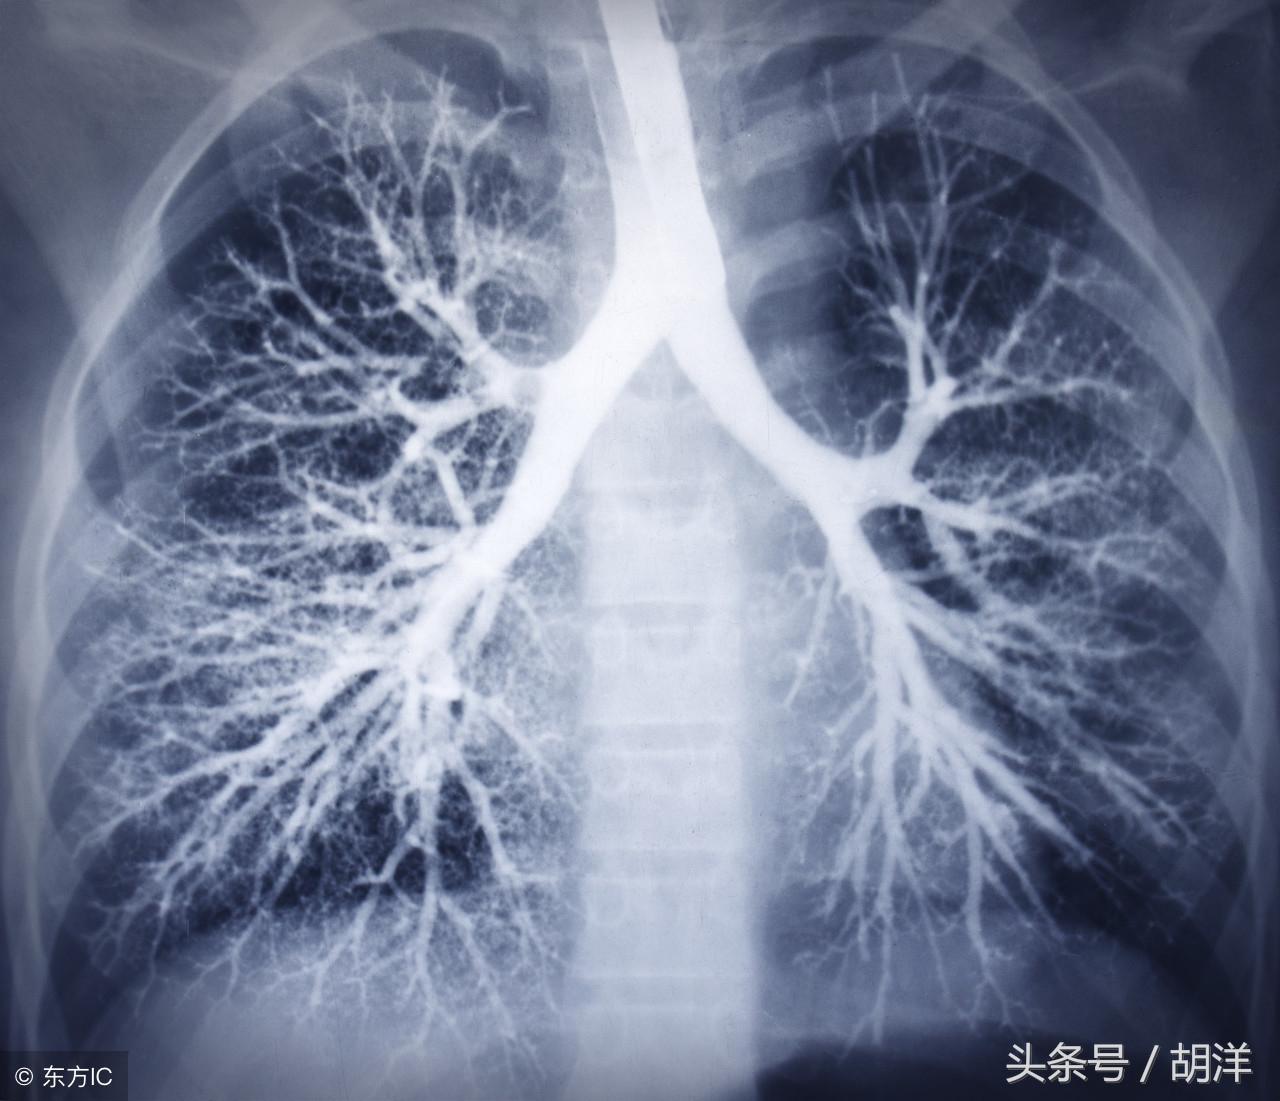

引起咳血的原因不仅仅是肺癌,有一种肺中长出的小球球可致大出血

咳血又称咯血,是呼吸科一个比较严重的症状,由于其可能提示肺部肿瘤等严重疾病而受到重视,但事实上在引起咯血的病因中,肺部恶性肿瘤所占的比例并不是很大,但很多人因咯血而焦虑异常,特别是咯血久治不愈情况下,更加令人无法正常的生活和学习,那么哪些疾病可能导致反复发作痰中带血或者咳出满口鲜血呢?

支气管扩张是一种支气管管壁结构破坏性疾病,正常情况下,支气管是一个带有弹性,拥有一定管径的能够维持正常呼吸通气的结构,当管壁结构受到破坏时,气管会受到被动的牵拉而扩张,管壁的血管由于弹性较小,容易被撕扯呈血管瘤改变,一旦胸腔内血流压力增大可能冲破血管瘤变薄的管壁而导致大咯血,少量渗血时则呈现为痰中带血。

曲霉菌是一种常见的真菌,正常情况下,曲菌很少感染肺部结构正常,免疫力良好的人群,当肺部受到破坏,特别是形成较大空洞和支气管扩张时,曲霉菌可以趁机进入空洞扩张的支气管内与其中渗出的白细胞、纤维素等成分形成球状结构,成为曲菌球,曲菌球在空洞内能够自由的活动,对空洞壁有机械性的损伤,当损伤到管壁变异的血管瘤时,极有可能导致大出血。